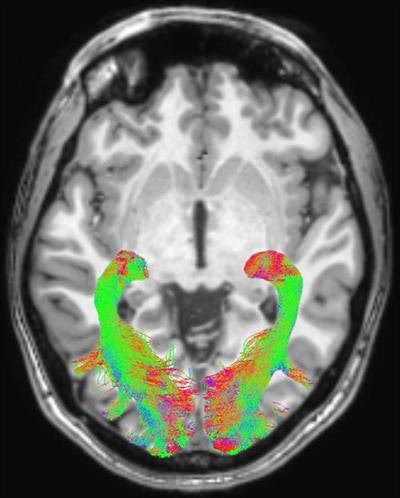

Three-tesla MRI scans (Achieva, Philips Healthcare) were performed on the healthy controls and patients, who underwent imaging within four weeks of their diagnosis. Arrigo and colleagues used DWI to assess white-matter changes and voxel-based morphometry to determine concentration changes of the brain's gray and white matter. All study participants also had ophthalmologic exams.

The group found statistically significant abnormalities within the visual system brain structures of patients with Parkinson's disease, compared with the healthy control subjects. These included changes in optic radiations, reduced white-matter concentration, and reduced optic chiasm volume.